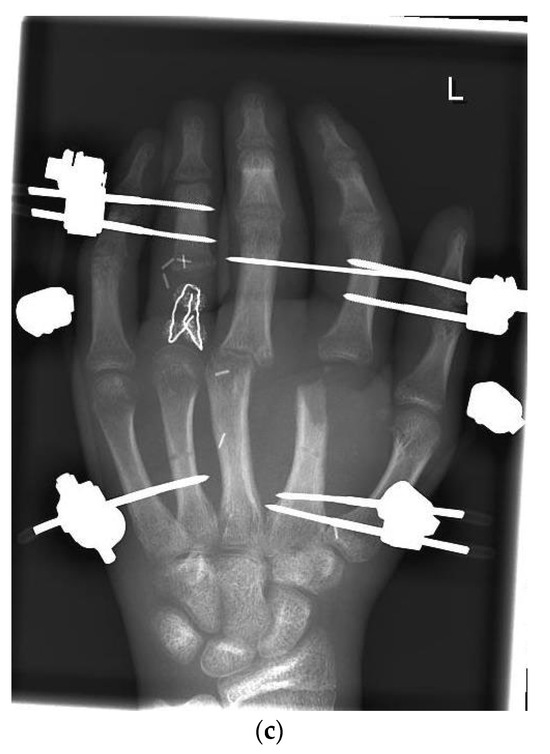

| 8 | 18 | m | Amputation of the left hand and complex multi-level injury of the left forearm | A. ulnaris reconstruction with vein interposition graft. N. medianus and N. ulnaris reconstruction with N. suralis interposition graft. Free ALT flap | FPD DII-DV 0–0–0–0 cm FNTD DII-DV 2–2–2–2 cm. Kapanji 5/10. Range of motion of the wrist: Extension/flexion 30–0–40°. Supination/Pronation 90–0–90° | Two-point discrimination: DI–III 6 mm, DIV 6–8 mm and DV 8 mm | No data |